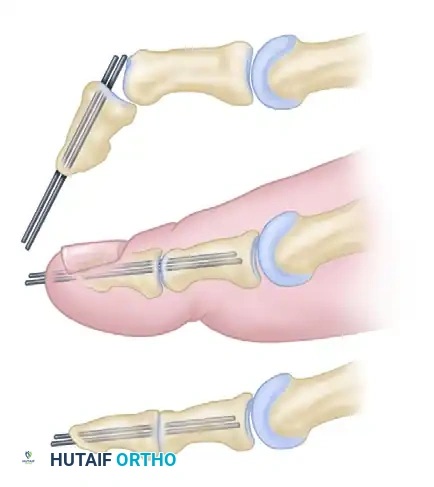

- Decision Matrix for the IP Joint:

- If neutral position is attained: Maintain the IP joint in a straight position using two longitudinal transarticular Kirschner wires (K-wires) or a single obliquely placed wire.

- If neutral position cannot be attained: Proceed to an IP joint arthrodesis. Resect the articular cartilage and enough subchondral bone from both the proximal and distal phalanges to allow the joint to sit flush in a neutral position.

- Pinning Technique: Drive the K-wires retrograde through the distal phalanx so they emerge 2 to 3 mm plantar to the nail bed. Then, drive them proximally across the IP joint into the subchondral bone of the proximal phalanx.

Note: Occasionally, the K-wires must cross the first MTP joint for added stability, though a properly applied bulky forefoot dressing usually holds the MTP joint in the correct position without transarticular MTP pinning.